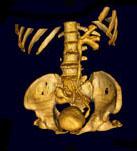

问题 男,65岁,反复发作的下腹部疼痛向会阴部放射伴血尿1 年余,CT如图所示,下列说法正确的是 ( )

选项 A、左侧输尿管扩张 B、考虑为先天性异位肾合并对侧输尿管下端结石 C、右肾窝内未见肾影,于盆腔入口处L~S水平见异位肾影 D、左侧输尿管在膀胱入口处可见一高密度结石影 E、左肾位置形态无异常